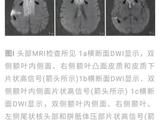

患儿女,41日龄,因“易激惹6d”于2017年4月天津市儿童医院神经内科住院。患儿易激惹、阵发哭闹,精神萎靡,睡眠不安,吃奶差,进行性加重,无抽搐,不伴发热、咳喘、吐泻。当地医院行头颅CT提示“双侧额、颞、顶、枕皮层下区、双侧桥脑、基底节区、丘脑多发性对称性低密度灶”(图1)。患儿为母亲第2胎第2产,胎龄39“周剖宫产出生,否认窒息史,出生体重3.0kg。父母健康,非近亲结婚;胞姐4岁,发育正常。

入院体格检查:体重4.3kg,头围36cm,身长52cm,神志清楚,精神差,易激惹,面容正常,前囟平软,心、肺、腹查体未见异常,注视不良,听反应迟钝,颈软,四肢肌张力增高,双侧膝腱、跟腱反射活跃,双跖反射伸性,拥抱及握持反射(-)。辅助检查:电解质、血气分析正常,肝、肾功能正常,4次血乳酸6.19-3.18(正常0.5-2.2)mmol/L,血氨正常;染色体46、XX;血串联质谱分析(MS/MS)及尿气相色谱.质谱分析(GC/MS)未见特异性异常;氨基酸分析正常。脑脊液:外观清,压力50mmH2O(1mmH2O=0.0098kPa),细胞及生化常规正常,乳酸1.54mmol/L。心电图、胸部x线片及腹部B超正常;脑电图:背景2-4Hz δ、θ波,双侧额、中央区棘波、尖波、尖-慢波;头颅磁共振成像(MRI)显示双侧丘脑、基底节区、脑干及双侧小脑、大脑半球白质区片状稍长T1、长T2信号影,于弥散加权(DWI)序列呈高信号(图2);视觉诱发电位(VEP)双侧视P100未引出,脑干听觉诱发电位(BAEP)示右侧外周段异常、左侧脑干段异常,四肢神经电图、肌电图未见异常。

入院后予口服硫胺素(维生素B1)6mg/(kg·d)及左卡尼汀、辅酶Q10等,静脉滴注能量合剂、银杏叶提取物注射液(商品名:金纳多)及脱水剂,维持内环境稳定,治疗第3天患儿易激惹状态好转,哭闹减少,吃奶、睡眠逐渐恢复正常,住院10d复查头颅MRI显示双侧基底节区软化灶,其余异常信号范围略缩小(图2),住院12d出院。出院后基因检查回报,发现患儿SLC19A3基因纯合变异:chr2:228566898(c.137T>C,p.Leu46Pro),为错义变异,其父母该位点均为杂合子(图3),该变异可能导致THTR2蛋白质功能受到影响,其致病性尚未见文献报道[参考数据库:人类基因突变数据库(HGMDPro)及PubMed];线粒体基因检测未见异常。据基因结果及临床表型确诊生物素-硫胺素反应性基底节病(BTRBGD),予口服生物素3mg/(kg·d),硫胺素增至24ms/(kg·d)。患儿3月龄时因痉挛发作半个月再次入院,复查头颅MRI示双基底节软化灶、双侧丘脑区T1稍高信号(图2),复查BAEP正常、VEP双侧P100可引出,复查血乳酸正常,予口服托比酯、静脉滴注甲泼尼龙治疗,痉挛发作逐渐减少,住院2周出院。随诊到4月龄时,痉挛发作停止,患儿吸吮困难、肌张力增高。再次出院后随访半年,精神、运动发育仍落后,无抽搐发作,复查脑电图示背景慢波,可以见到多灶性痫性放电。